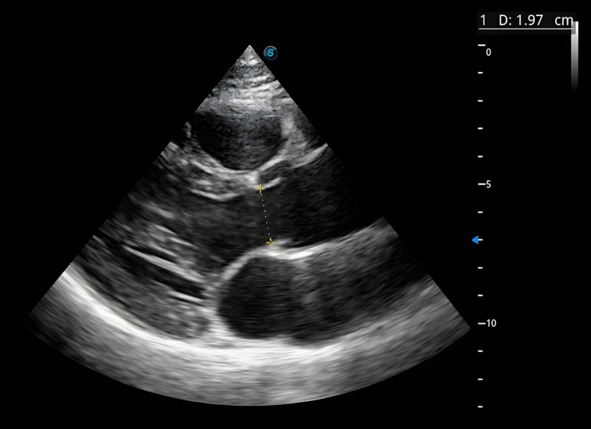

Все измерения в эхокардиографии важно производить в определенную фазу сокращения: в диастолу или в систолу. Первое измерение в этом доступе – фиброзное кольцо аортального клапана, его мы проводим в пик систолы. Для этого мы фрезуем изображение и отматываем видеопетлю на тот момент, когда створки аортального клапана открыты. Берем калипер и делаем измерение: размер фиброзного кольца составил 1,97 см (рис.2).

Рис.2